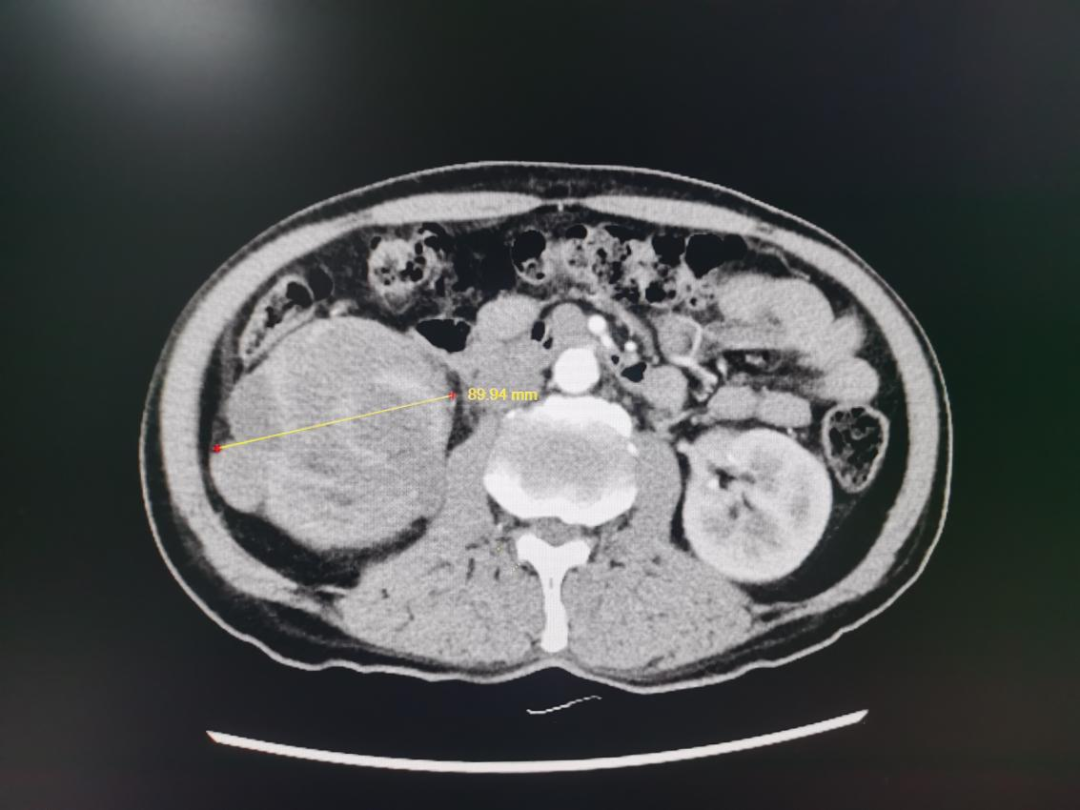

患者薛某一周前在我院内分泌科就诊,偶然检查发现右肾巨大占位,随即联系泌尿外科进行会诊。泌尿外科仲委主任组织科室人员对患者的影像学检查仔细研读,经多方面考虑,建议患者进一步手术治疗。

“如此巨大的肾癌肿瘤十分少见,且肿瘤位于肾门部,毗邻重要脏器及多条血管供应,手术难度大,风险高”。仲委主任表示,由于肿瘤体积较大导致手术可操作空间狭小,稍有不慎就会造成血管、脏器损伤而引起大出血,如肿瘤侵犯和黏连周围器官,手术的难度和风险将大大增加。